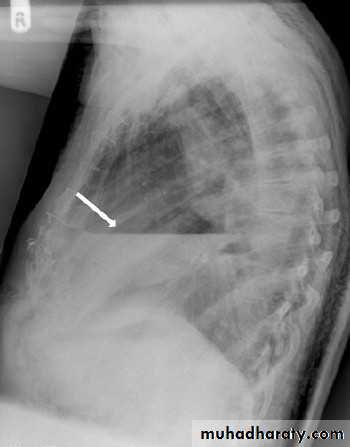

A lateral (or decubitus) projection is recommended if the initial chest x ray is inconclusive.

Diseases of the Pleura Dr.Mustafa Nema. Baghdad College of Medicine 2013